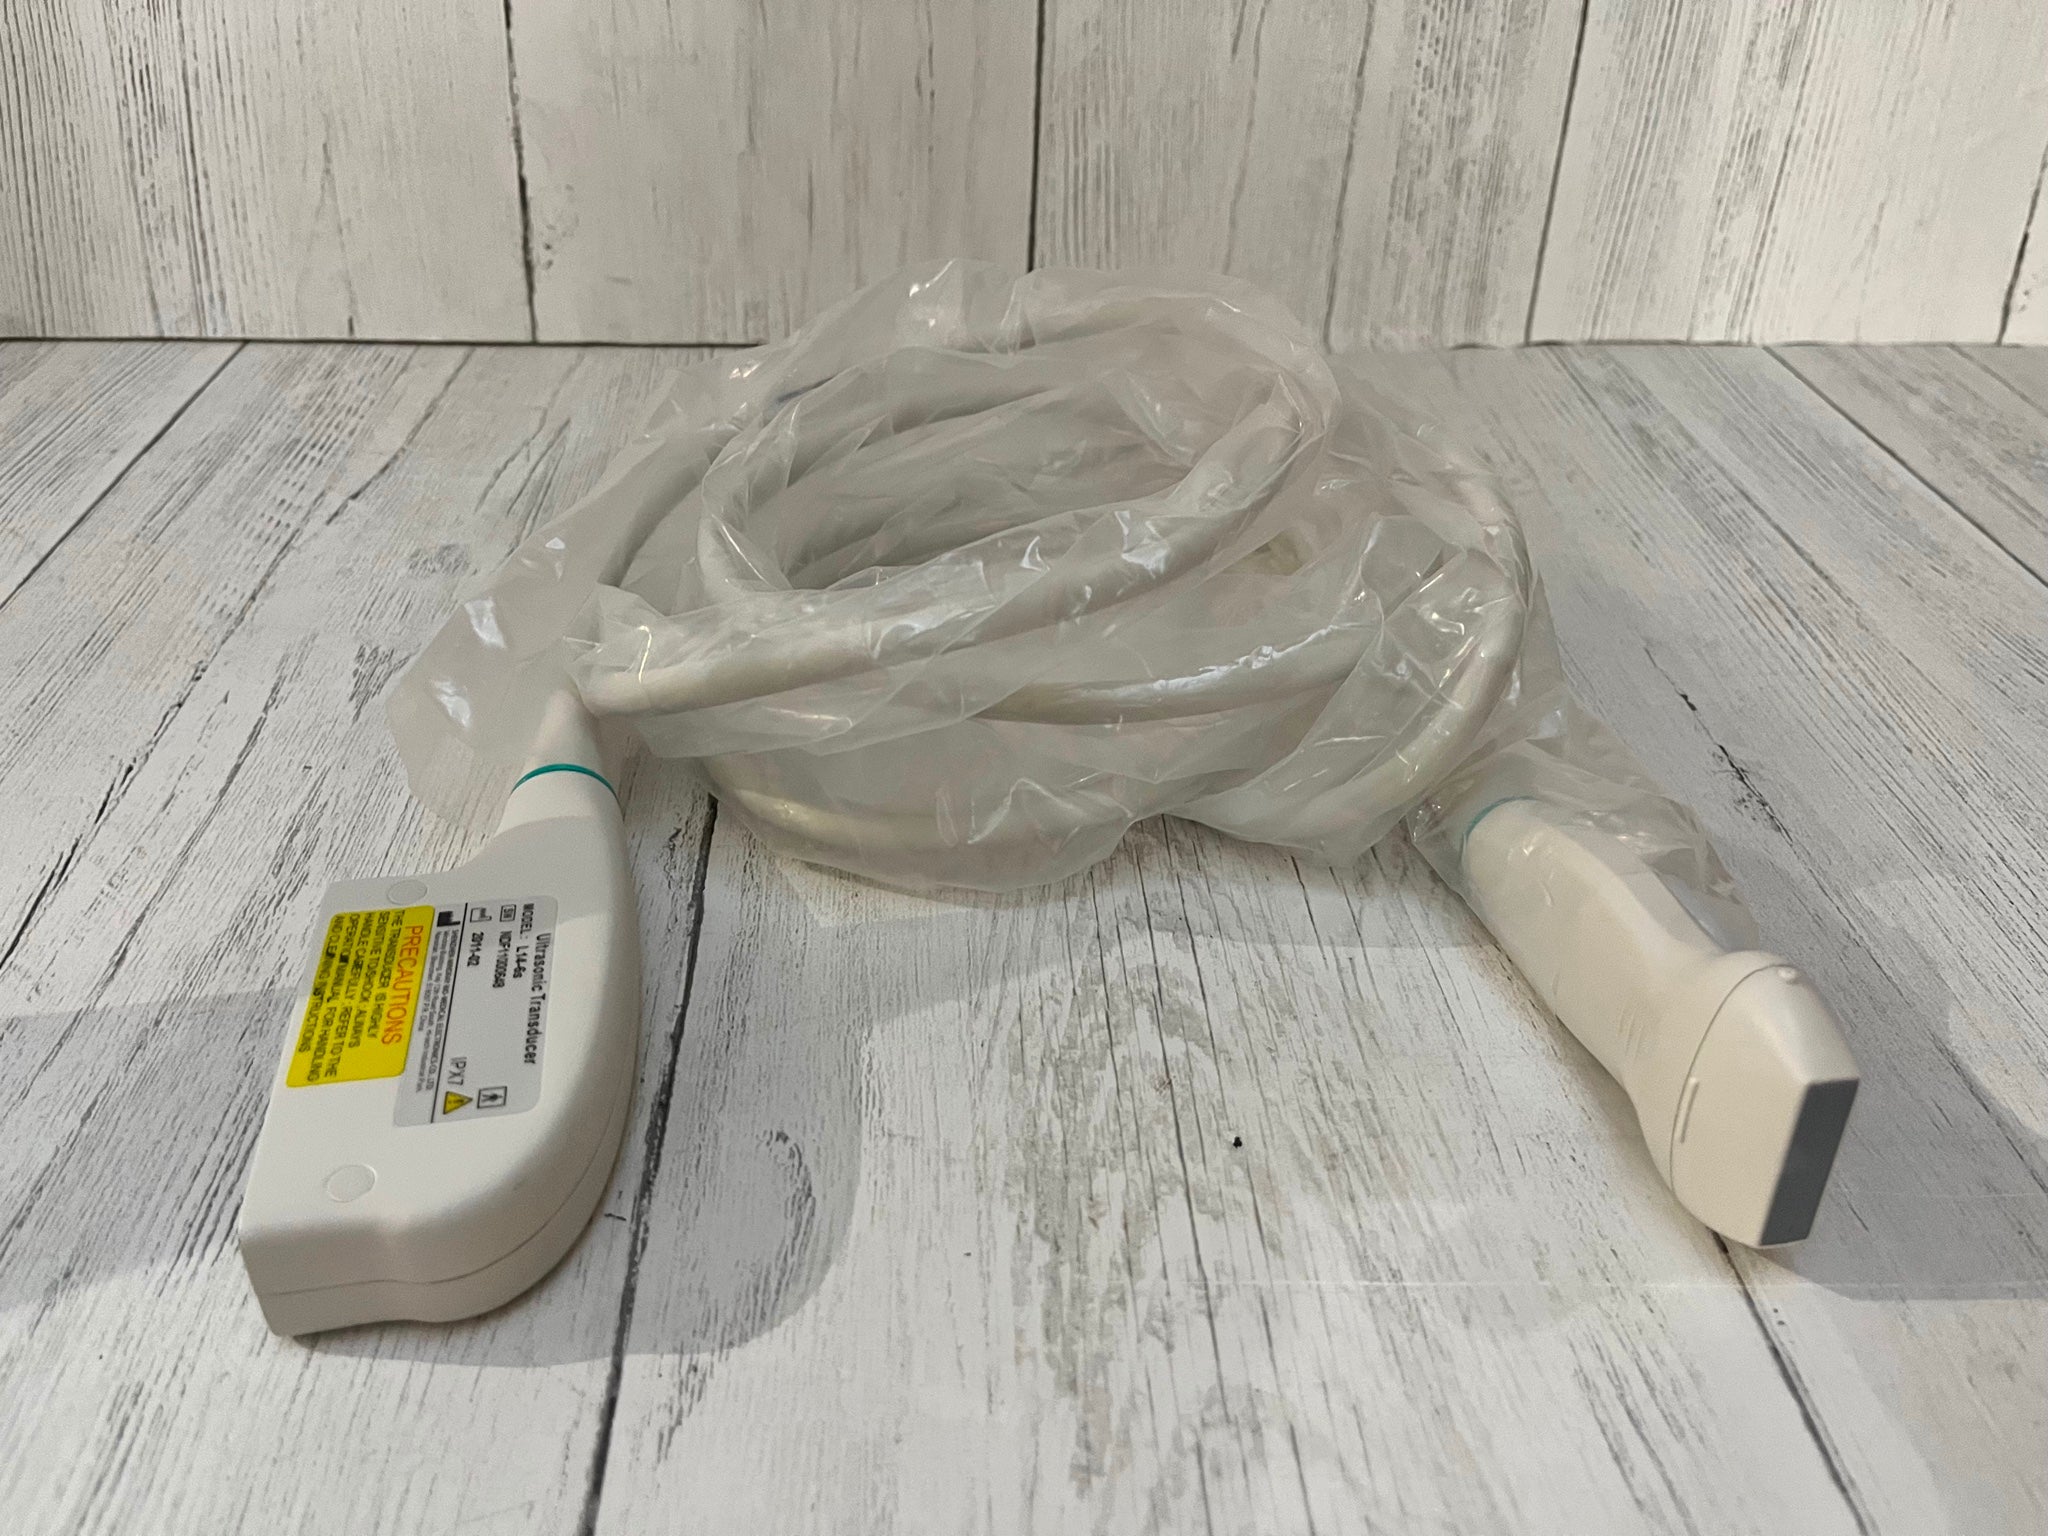

Acuson L5 probe , Ultrasound Transducer Siemens

Sale price$ 1,415.30